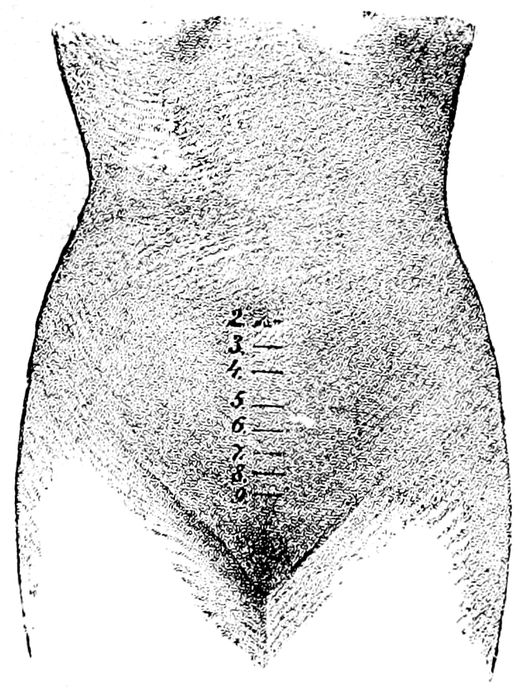

| 27. |

Abdominal enlargement at different months of pregnancy |

63 |

| |

| 28. |

Height of the uterus at various months of pregnancy |

64 |

Fig. 27.—Abdominal enlargement at third, sixth, ninth, and tenth months of pregnancy. (Williams.)

Fig. 28.—Height of the uterus at various months of pregnancy. (Bumm.)